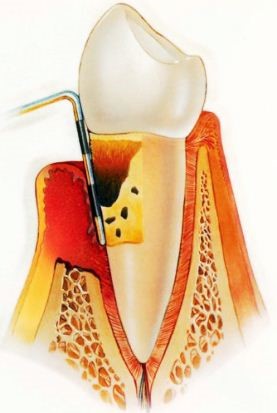

- При работе машинным бором врач может перфорировать стенку канала. Исправление перфорации требует дорогостоящих материалов. По правилам это делается за счет клиники. Поэтому вначале действуют ручным бором.

- Перфорация — еще один вариант осложнения после периодонтита. Только контроль движений способен обезопасить от перфорации. Направление движение иголки должно соответствовать оси зуба. Для контроля процесс, чтобы не возникли осложнения после периодонтита, постоянно отслеживают. Он осуществляется при помощи рентгенограммы в ходе расширения. Вводят корневую иголку и снимают зуб на рентгенограмме вместе с ней. По окончании расширения тоже делают рентгенограмму. Если во время обработки канала становится больно — нужно прекратить работу. После этого проверяется положение инструмента в зубе. Боль иногда возникает, если инструмент коснулся периодонта с последующей перфорацией.

- Перфорация затрудняет последующую пломбировку. Если не заметить перфорацию, возникнет очаг воспаления. Именно такие осложнения пульпита и периодонтита возникают спустя месяцы после лечебных мер. При исправлении нельзя пломбировку внедрять в периодонт через перфорацию. Ее пломбируют цементом, вводя у корня зуба.